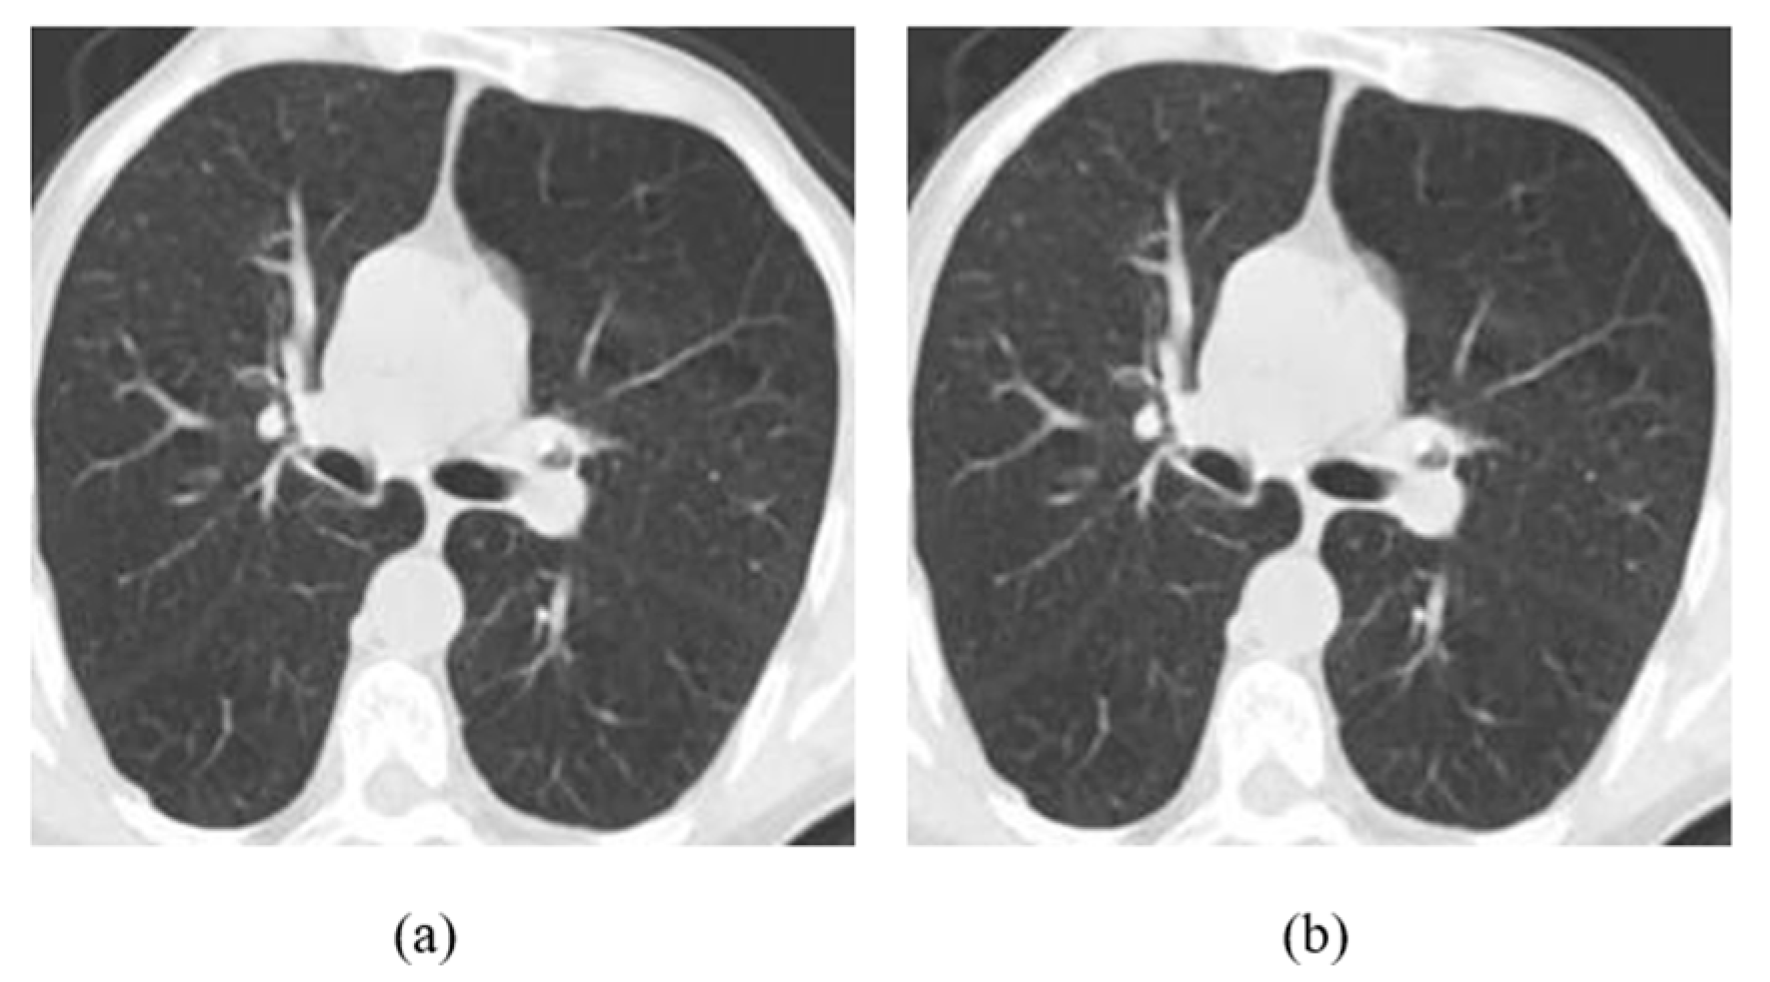

According to the results, CT-Scan was the least robust modality, as the accuracy of the models was reduced almost by 50%. This is very interesting, as COVID-19 detection using CT-Scans should have been the most robust problem because it has only two classes. Even with the smallest perturbation, MobileNetV2 was decreased by 12.2% in terms of accuracy (Figure 9). The CT-Scan modality should be further investigated to draw safe conclusions. The problem of brain tumor classification was the most difficult one and therefore the performance of the models, even with clean images, was low. However, the models did not lose significant accuracy with an imperceptible perturbation. On X-rays, accuracy decreases significantly when we increase the embedding strength, or we insert a lot of information.

Figure 9.

(a) Clean Image, (b) Attacked image (L-Bit = 100, Embedding strength = 50).